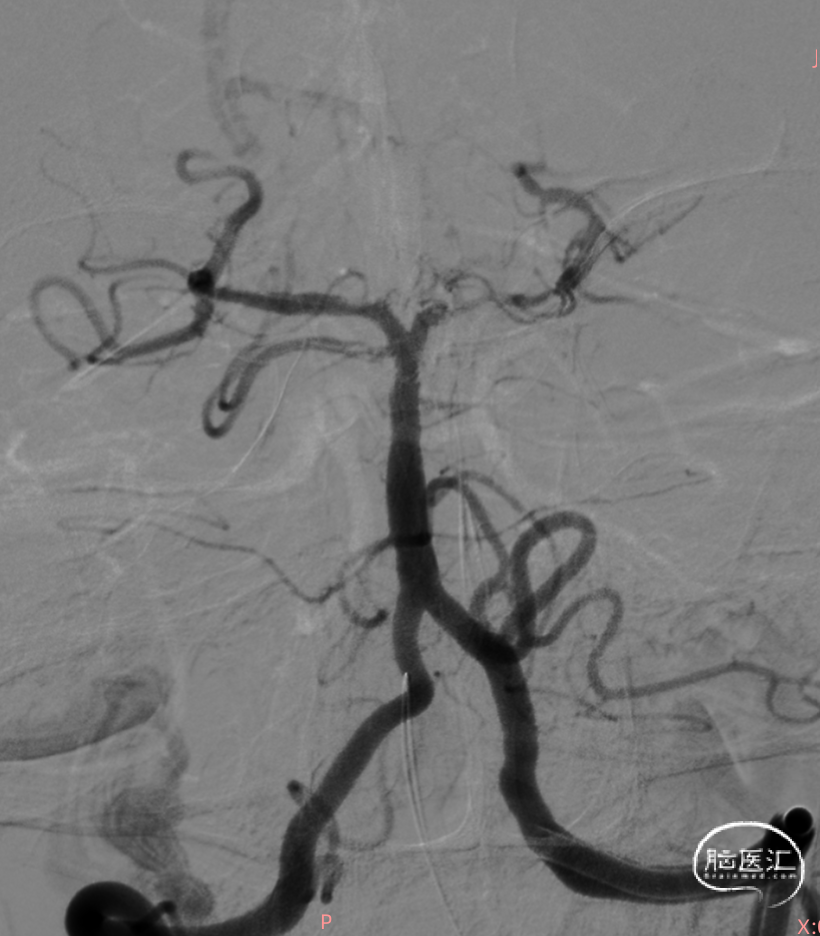

微导丝携带微导管至右侧大脑后动脉P3段,抽拉结合取栓一次见右侧大脑后动脉再通。

微导丝携带微导管至左侧大脑后动脉P3段,抽拉结合取栓一次见左侧大脑后动脉再通。

左侧大脑后动脉P1段发白,观察20min较前好转,血流状态维持良好,结束手术。